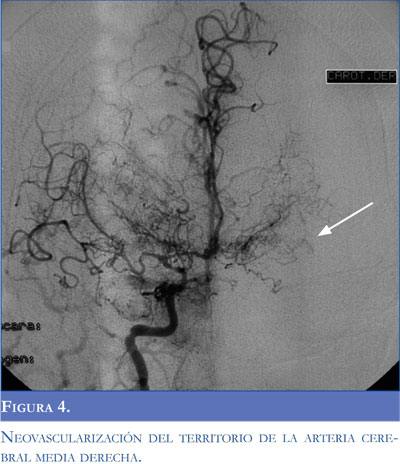

Una arteriografía realizada durante la primera semana de evolución mostró estenosis de la carótida izquierda con adelgazamiento distal de la vascula-tura cerebral con neoformación y colateralización de circulación externa con la interna conformando un patrón típico de síndrome moyamoya (Figuras 3, 4, 5 y 6). El control imagenológico hacia los 15 días de hospitalización evidenció una disminución del 50% en el volumen del sangrado intraventricular. La paciente logró llegar a un alertamiento espontáneo sin contenido de la conciencia ni respuesta al llamado. A los 45 días de evolución logra salir de UCIN con traqueostomía percutánea y nutrición por gastrostomía.